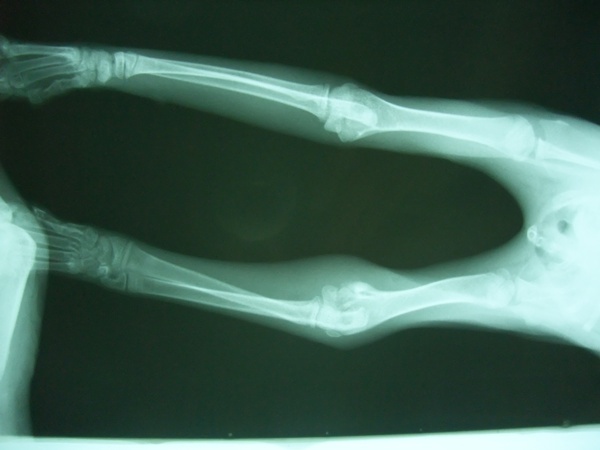

主題: 手腫腫的小賓士 申請者姓名: 陳青 花色: 申請日期: 2012-08-25 02:26:32 申請者部落格: 申請者臉書網址: http://www.facebook.com/ching.chen.39 所在縣市/合作醫院: 台南市/奇異果動物醫院 治療費用: 9160元 需求人數: 20人 已結案 (2012-12-08 19:14:10) 報名人員: Yun Chen(已付款)、Leo Lee(已付款)、Amber Tsai(已付款)、Denbe Yangchen(已付款)、陳阿妹(已付款)、Tina(已付款)、王興賢(已付款)、崔太(已付款)、小黑仔(已付款)、Georgina Chen(已付款)、詹小乖(已付款)、Bonnie Huang(已付款)、Amy(已付款)、Chivas(已付款)、胡同貓(已付款)、Cecilia Chang(已付款)、Chun-Kuan Lin(已付款)、心上人(已付款)、陳倩婷(已付款)、Yuan Yu(已付款)、 候補人員: 小舟、小舟、 動物病情說明: 小賓士疑似被同類咬傷

可憐的孩子全身都是傷口...

尤其是左前肢部位最嚴重,還造成關節部位化膿

因為被咬傷的部位在關節,有角質增生情況

所以日後康復可能還是會有點腫腫的,但是不會影響行走動物近況說明: 通報人幫小貓找到認養人了...